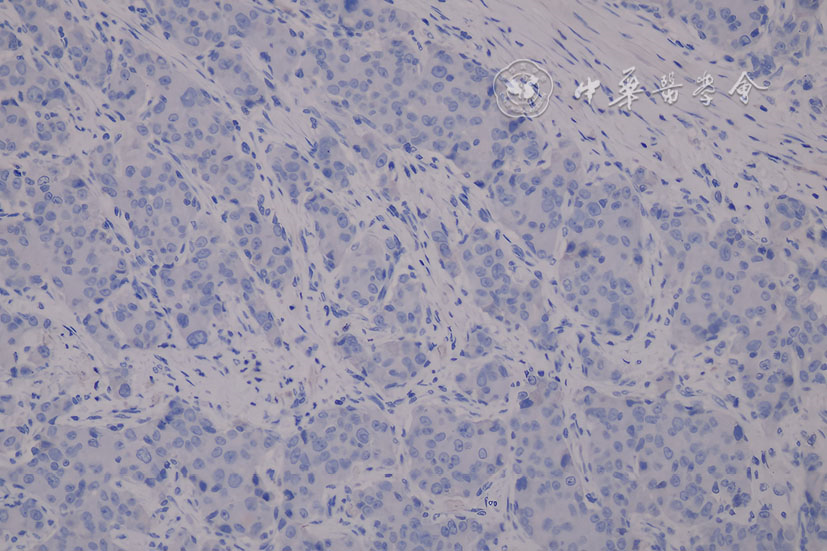

图5 男性隐匿性乳腺癌患者右侧腋窝皮下肿块切除术后免疫组织化学图(EnVision ×200) 注:显示CK20(-)